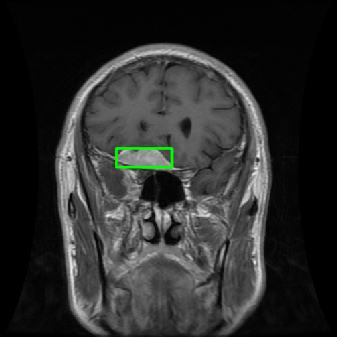

From the above discussions, we have discovered the significant potential of applying Retinex theory to image segmentation and explored its fundamental differences from traditional models. Traditional image segmentation models typically focus on the impact of intensity information on the segmentation results. Therefore, when faced with complex segmentation scenarios, the segmentation results are often affected by lighting, artifacts, and unclear boundaries in the image. As shown in Fig. 1, we present the results of the classical local model LIF [ZHANG20101199] for segmenting brain tumor images along with surrounding tissue edema. The irregular ring-like enhancement caused by the edematous tissue leads to irregular boundaries and low contrast in the images. Consequently, the LIF model can only identify the central necrotic and liquefied regions of the tumor, failing to detect the boundaries and becoming trapped in local minima. In this paper, we draw inspiration from the Retinex theory, which is widely applied in the field of image enhancement. According to Retinex theory, the reflectance component characterizes the intrinsic structural properties of the observed image and preserves texture information independent of illumination variations. By integrating this reflectance component into the level set framework, our model achieves robust segmentation of medical images even under severe intensity inhomogeneity. In addition, a linearized Structural-Prior is proposed to restore intensity consistency and capture local geometric features, thereby improving boundary localization in complex or blurred regions. Furthermore, a relaxed binary level set representation is employed to enhance robustness against noise and to enable accurate tracking of complex contours. Based on these innovations, we propose a novel variational reflectance-based level set model (RefLSM) that simultaneously corrects bias fields and performs segmentation. Experimental results demonstrate that RefLSM significantly outperforms conventional level set methods in both segmentation accuracy and robustness. We present the results of our model segmenting the two brain tumor images mentioned above in Fig. 2.

Fig. 4 displays the visual comparison results for segmenting eight brain tumor MR images between the RefLSM and three representative models: the RESLS [8765635], ALF[MA2019201], and L1 model[LIU2019193]. These images exhibit severe intensity inhomogeneity and noise attributable to inconsistent bias field and imaging equipment. The initial level set function (LSF) initialization was consistent across all models, as shown in Fig. 4 (a), which illustrates the initial placement of the zero level contour. For visual clarity, we included the ground truth in Fig. 4 (f). The segmentation outcomes from the RESLS, ALF, and L1 methods are presented in Fig. 4 (b), (c), and (d), respectively.

It is evident from the first and last columns of Fig. 4 (b) that the ALF model tends to become trapped in local minima under severe intensity inhomogeneity. Furthermore, segmentation results presented in the columns 1-4 of Fig. 4 (b) and (c) reveal that both the ALF and L1 models mistakenly segment small isolated or irrelevant regions due to the effects of irregular intensity patterns. Additionally, when weak boundaries are present, as seen in the 1st and 3rd columns of Fig. 4, the RESLS, ALF, and L1 methods fail to accurately identify object boundaries. Consequently, the zero level contours of these models deviate significantly from the objects throughout the level set evolution, causing drastic misalignment after further iterations.

In stark contrast, our proposed method exhibits greater robustness against images exhibiting severe intensity inhomogeneity and weak boundaries. The proposed prior constraint term effectively corrects for intensity inhomogeneity, while the proposed binary level set adeptly reduces noise during the segmentation process.

Overall, these findings demonstrate that the segmentation outcomes produced by our model are more accurate. Besides visual assessment, we calculate the Dice and Precision values of evaluated models for brain tumor segmentation in table 1. Based on these results, we draw a boxplot with scatterplot overlay, as shown in Fig. 6, which displays the data distribution and facilitates comparison of different models’ performance across various brain tumor MR images. We analyze the maximum, median, and minimum, which correspond to the best, median segmentation results, and worst segmentation results, respectively. It is clear that the RefLSM achieves more accurate segmentation results compared to the other models. Moreover, the smaller range of the RefLSM in the boxplot indicates robustness and stability to different images of the brain tumor.